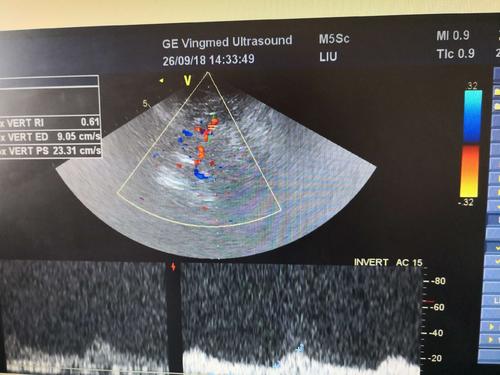

經(jīng)顱彩色編碼雙功能超聲TCCD成像模式分析

經(jīng)顱彩色編碼雙功能超聲,區(qū)別于經(jīng)顱多普勒超聲,它的英文簡(jiǎn)稱是TCCD,后者是TCD。TCCD成像模式是什么樣的,tcd廠家澳思泰今天來分析這一問題。

TCCD成像模式

(1)依據(jù)多普勒頻移值編碼成像即f-TCCD:

依賴運(yùn)動(dòng)紅細(xì)胞所產(chǎn)生的多普勒頻移值進(jìn)行計(jì)算機(jī)編碼,可以顯示血流方向和測(cè)算血流速度,需要校正多普勒取樣角度,角度及篩查深度依賴性較大,較易產(chǎn)生運(yùn)動(dòng)偽像。

經(jīng)顱彩色編碼雙功能超聲TCCD成像模式

(2)依據(jù)運(yùn)動(dòng)紅細(xì)胞所產(chǎn)生的總能量進(jìn)行編碼成像即p-TCCD:

只與運(yùn)動(dòng)紅細(xì)胞所產(chǎn)生的總能量有關(guān),無需校正多普勒取樣角度,對(duì)于受取樣角度影響較大血管病變,諸如大腦后動(dòng)脈(PCA),大腦中動(dòng)脈(MCA)M2段,大腦前動(dòng)脈(ACA)A1段有一定的幫助作用,信噪比更高,不易產(chǎn)生混疊效應(yīng)。p-TCCD相對(duì)f-TCCD而言,缺點(diǎn)是不能顯示血流方向,對(duì)顯示狹窄處高速血流敏感性較低。